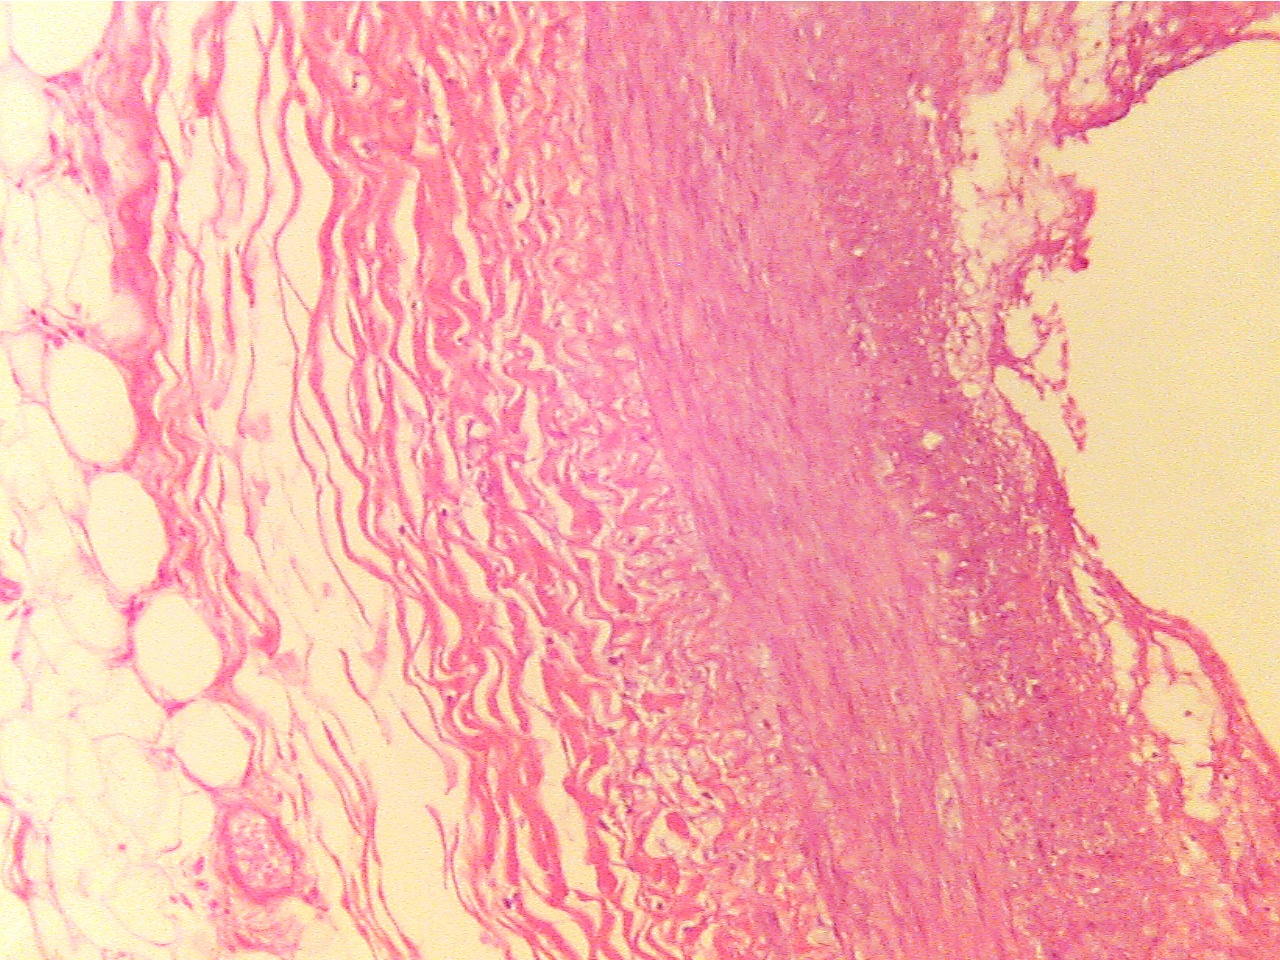

Fibrous plaque (100X2.0 - c1)

Layers are areolar tissue (left), externa (red collagen

Amorphous

acellular material (upper left) and cellular

fibers), smooth muscle (thin red middle layer), tunica

and

fibrous plaque (center) replace intima and smooth muscle,

intima (blue granular layer), fibrous plaque

(thick, pink),

externa (collagen fibers) remains at lower right

endothelium (thin layer along lumen), lumen (at right)